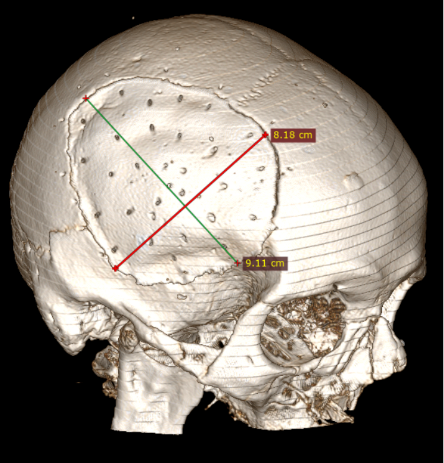

Straipsnyje aptariamu atveju paciento KPL skirtinas mažiausiai (75 cm2) grupei, kuriai būdinga minimali infekcijos atsiradimo rizika (13 pav.), tačiau operacijos metu vis tiek buvo paimtas mikrobiologinis pasėlis infekcijai ekskliuduoti. Mokslinėje literatūroje taip pat pristatomas siekis tirti skirtingų pirminių galvos smegenų hematomų, po kurių reikėjo atlikti kraniektomiją, koreliaciją su EDS, tačiau reikšmingų rezultatų negauta [8].

13 pav. Kranioplastikos lopo dydis (iki 75 cm2)